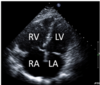

21.2 The image below on the left shows a normal central venous pressure (CVP) trace. The CVP trace in the image below on the right is most consistent with a) AF b) MR c) AR d) TR e) Pericardial constriction

TR